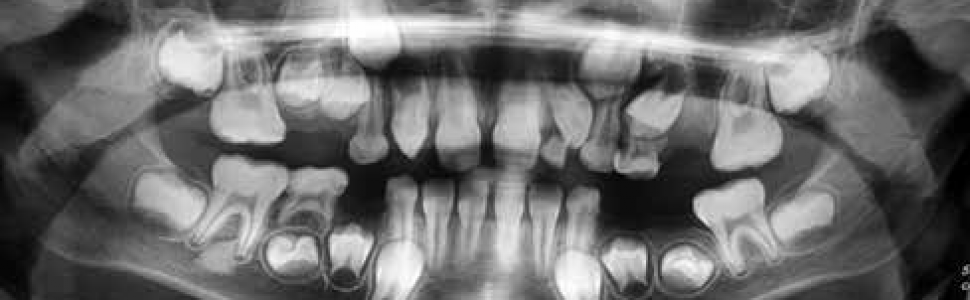

Zęby wgłobione to jedna z najczęściej występujących anomalii budowy zębów. Częstość występowania tej nieprawidłowości jest szacowana nawet na 10%, a polega na wpukleniu tkanek zmineralizowanych w obręb korony klinicznej lub kanału korzeniowego zęba z tworzeniem niejednokrotnie formacji tkanek z własnym oddzielnym wierzchołkiem i otworem bocznym lub wierzchołkowym. [...] Jeżeli ząb wgłobiony jest przyczyną estetycznych i funkcjonalnych nieprawidłowości, kiedy nie ma szans na skuteczne leczenie endodontyczne, istnieją wskazania do ekstrakcji. W niniejszej pracy opisano przypadek skutecznego leczenia zęba wgłobionego, który był zębem przyczynowym ropnia dołu nadkłowego.